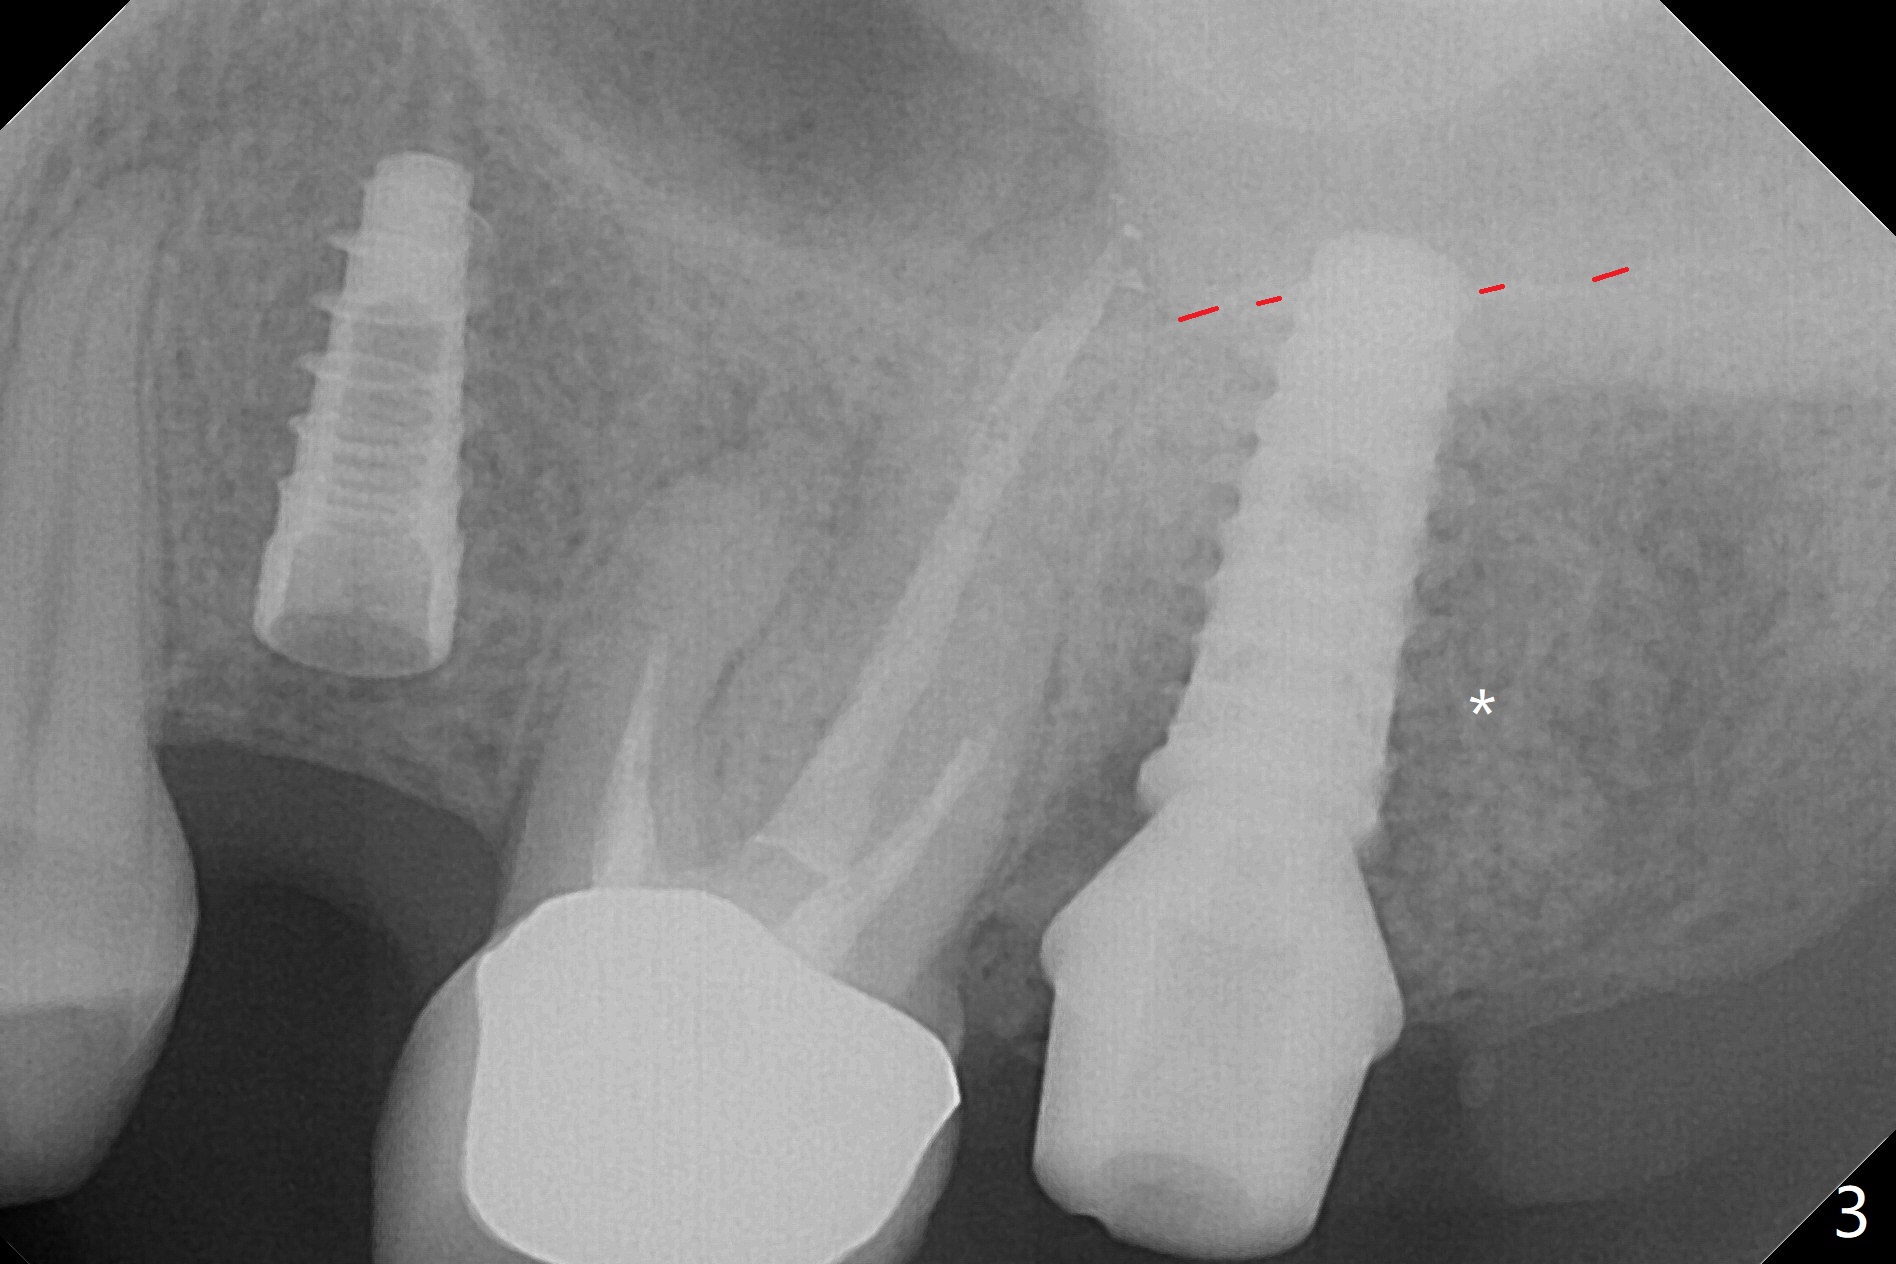

The palatal gingival margin of the tooth #15 with vertical root fracture is low, consistent with the low palatal plate after extraction (Fig.1 >). With IS guide, a 5x11 mm IBS implant is placed in the septum with >5 mm the palatal gap. After underprep in depth, a 3.5x9 mm achieves primary stability (Fig.2,3). The palatal defect is repaired with allograft (*) and 2 pieces of PRF membrane. The palatal soft tissue defect appears to have been repaired 6 months postop (Fig.4,5). When a narrower abutment with longer cuff is placed at #15 (6x4(4) mm in Fig.6, as compared to 6.5x4(3) mm one in Fig.2), there is no gap between the implant and abutment. In contrast there is one at #13 (Fig.6 <) when a 4x4(4) mm abutment is seated following removal of a 4x4 mm healing abutment. After use of a 4.6 mm profile drill, the gap disappears (Fig.7). Impression is taken.